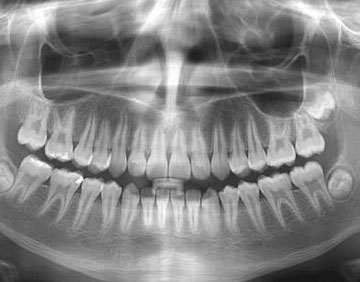

Ağız içi hastalıklarının -özellikle diş ve çene kemiği gibi sert doku ile ilgili olanların- teşhisinde en büyük yardımcımız dental radyografiler yani diş filmleridir. Diş filmlerinin de en çok kullanılan iki tipi periapikal (2-3 dişi birlikte gösteren küçük filmler) ve panoramik filmlerdir (alt ve üst çene dişleri ile çene kemiklerinin tamamını gösterebilen büyük filmler). Bilgisayar destekli bir teknik olan dijital radyografi cihazları da çok düşük radyasyon dozu kullanarak film görüntüsü üzerinde renk ve ışık oynamaları yapmaya imkân kılarak ayrıntılı değerlendirme yapmamıza olanak tanır. Bunların yanında, özellikle implant uygulamaları ve eklem hastalıklarının teşhisinde, MR ve BT de teşhise yardımcı olarak hastadan istenebilecek diğer filmlerdir.

Tüm bu yöntemlerle ancak 1/3’ü ağız içinde görülebilen diş yapısının geriye kalan bölümü ile çene kemiği içinde kalan iltihabi oluşumları ve gömülü diş gibi yapıları rahatlıkla görüp teşhis edebiliriz. Tabii ki iyi bir teşhis de doğru tedavi planlamasının yapılabilmesine olanak verir. Böylelikle gerekli tüm tedavi ihtiyaçları erken teşhis edilir ve ileride daha büyük sorunlar oluşması önlenir. Oral Diagnoz ve Radyoloji departmanında, hasta dosyasında bulunan kişisel ve tıbbi bilgileriniz, gizlilik politikamız gereği üçüncü şahıslarla asla paylaşılmaz. Oral Diagnoz ve Radyoloji departmanında tüm hastaların ilk kayıtları alındıktan sonra muayeneleri ayrıntılı olarak yapılmaktadır. Daha sonra tedavi ihtiyaçlarına uygun olarak diş filmlerinden bir ya da birkaçı alınmakta ve tüm tedavi planlaması tespit edilmektedir. Yapılan tedavi planlamasına uygun olarak hastalarımızı konularında uzman hekimlere yönlendirip tedavileri derhâl başlatılmaktadır. Hastalarımızın tedavi planı ve süresi ile ilgili tüm sorularına cevap vermek de departmanımızın görevidir.

Diş röntgeni diş, çene kemikleri ve diş eti seviyesinin klinik muayenede görülmeyen kısımları hakkında fikir edinmek amacıyla X ışını yardımıyla elde edilen radyolojik görüntülerin adıdır.

Radyolojik teşhis amaçlı iki farklı diş röntgeni çeşidi olup bunlar tüm ağzın ve dişlerin bir arada görüldüğü panoramik röntgen filmi ve dişlerin tek tek görüldüğü periapikal röntgen filmidir. Diş filmleri analog film üzerine basılabileceği gibi RVG ve fosfor plak gibi arayüzler yardımıyla digital olarak da görüntülenebilmektedir. Ayrıca özellikle çene cerrahisi ve implant uygulamalarında gerektiğinde hastadan çene kemiklerinin tomografisi de istenebilmektedir.